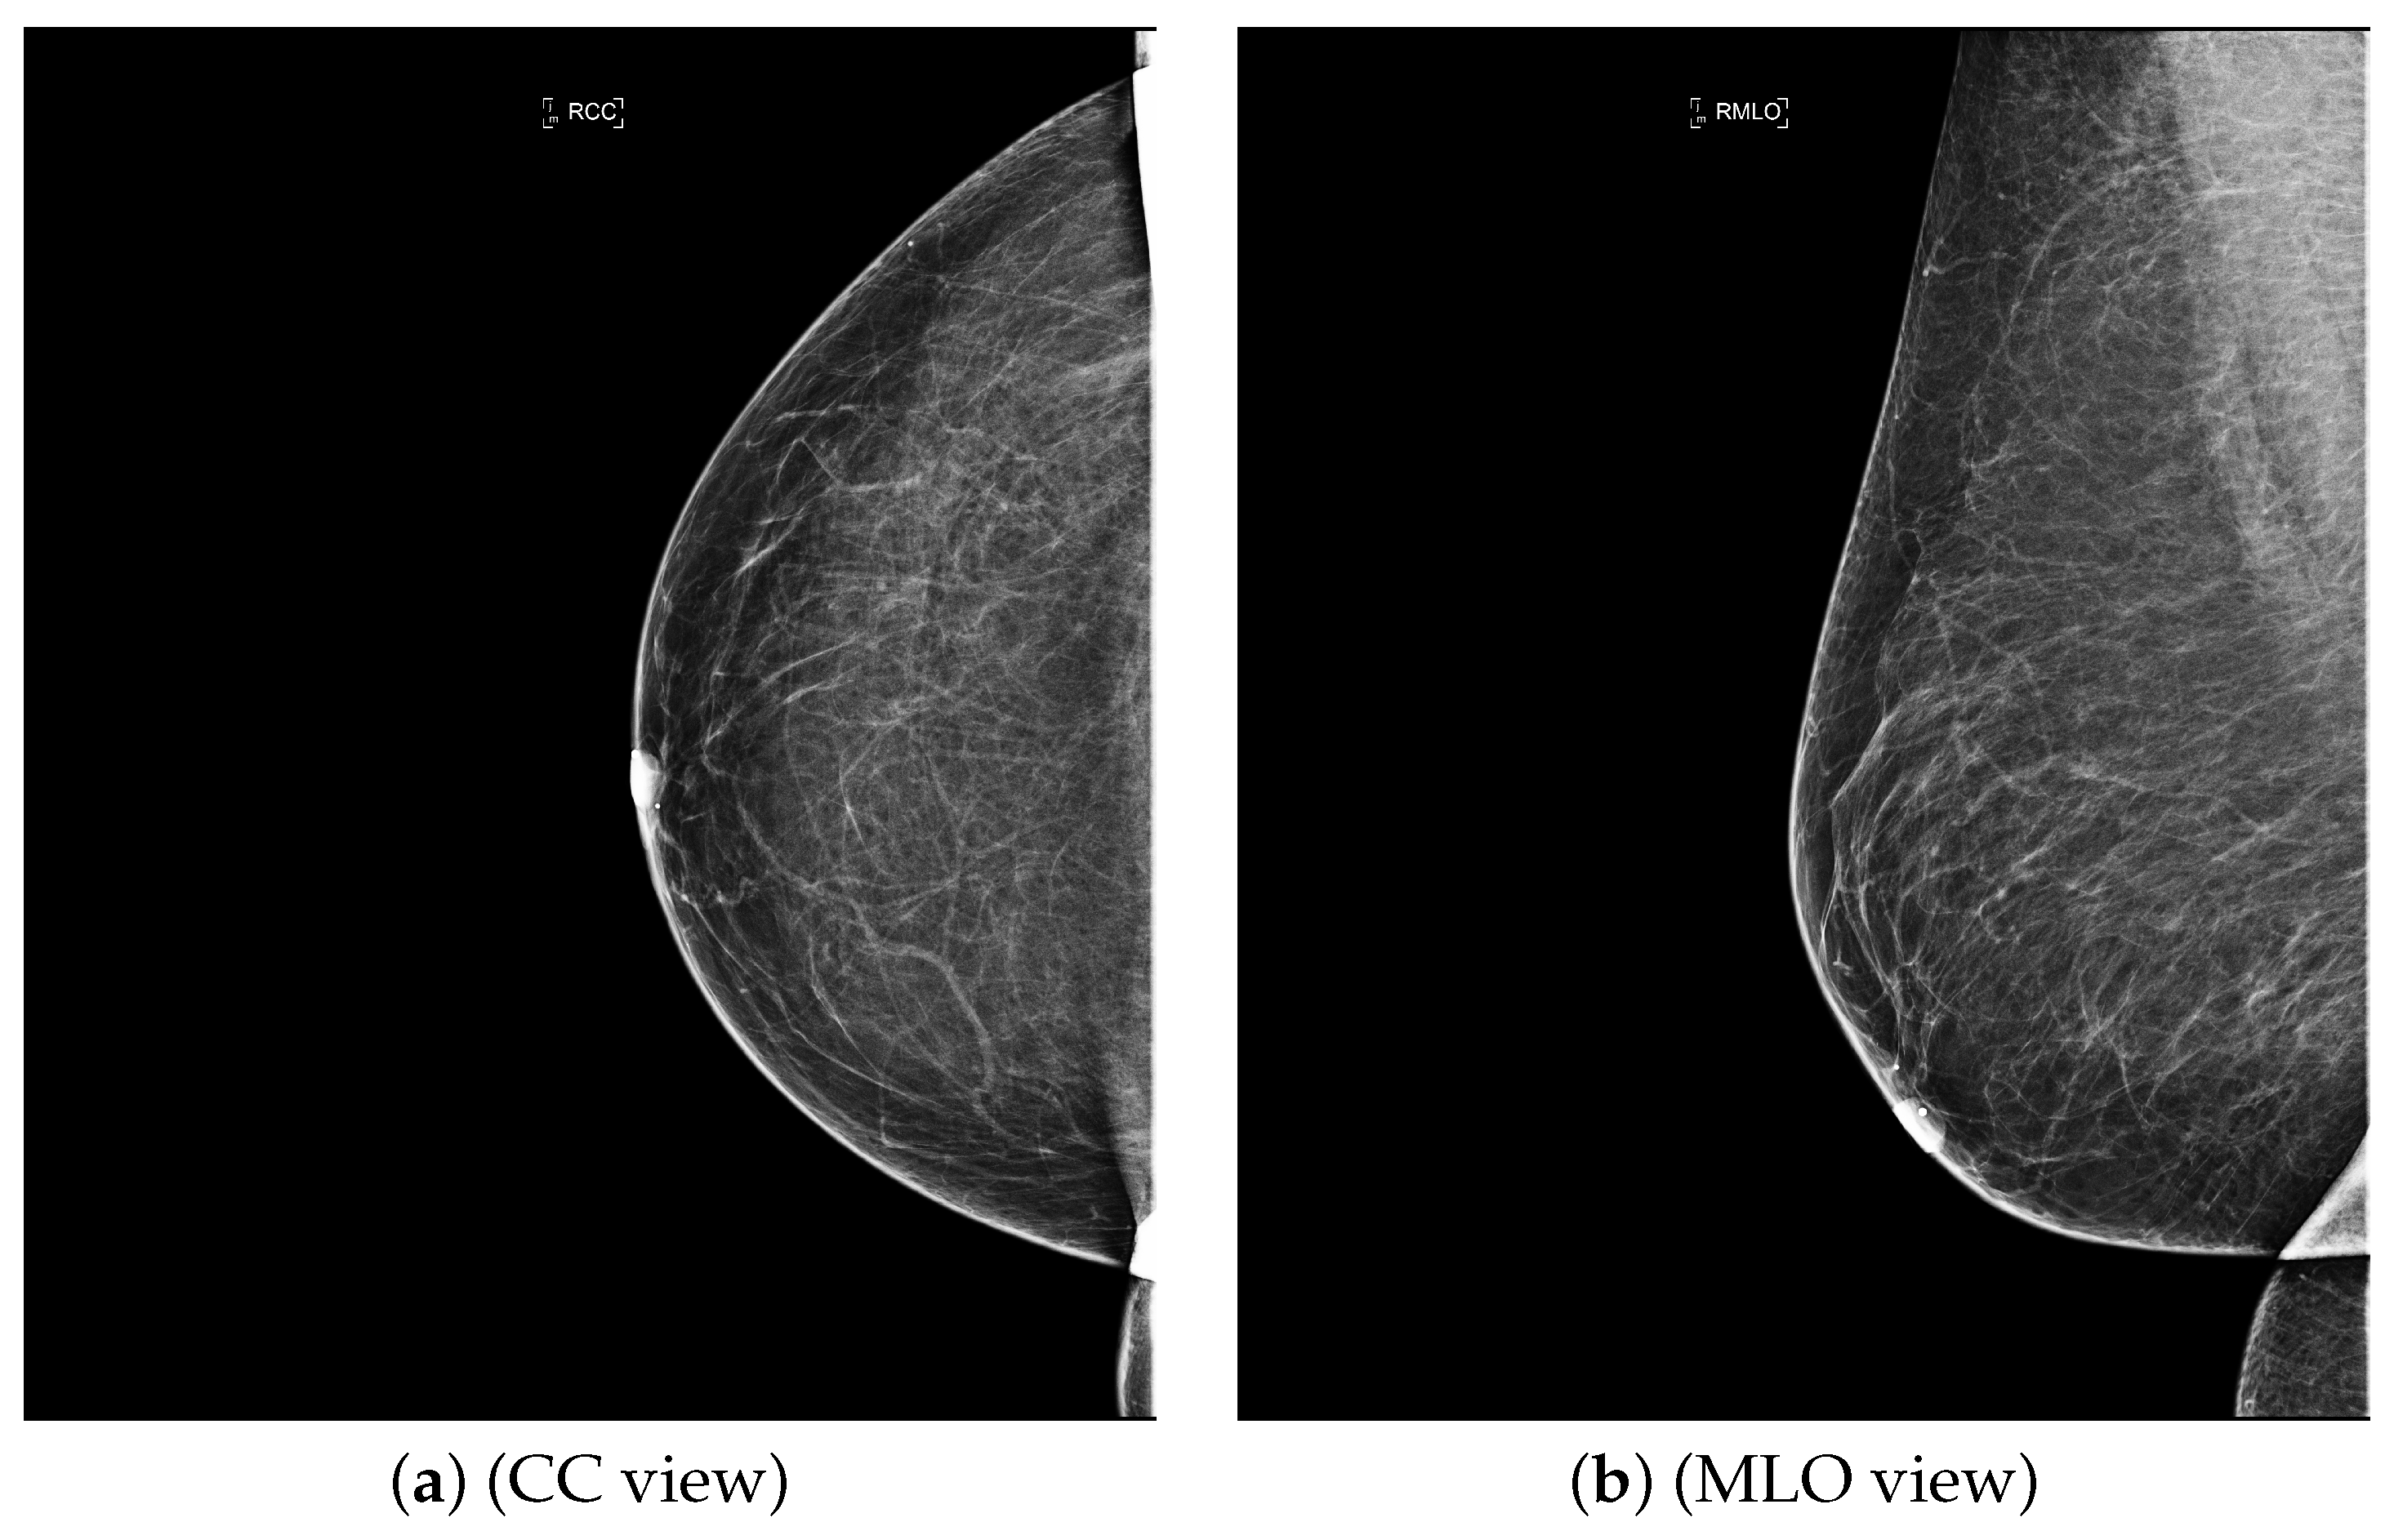

| ACR Class | Feature | Tissues Proportion | Example |

|---|---|---|---|

| A | Fatty | Less than 25% dense tissue | ![]() |

| B | Fibro-glandular | 25–50% dense tissue | ![]() |

| C | Heterogeneously dense | 50–75% dense tissue | ![]() |

| D | Extremely dense | More than 75% dense tissue | ![]() |